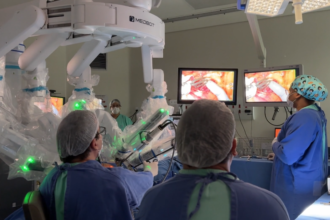

Veja imagens de cirurgia feita a 2.700 km de distância em paciente do SUS

O Hospital do Amor, que fica na Amazônia, em…